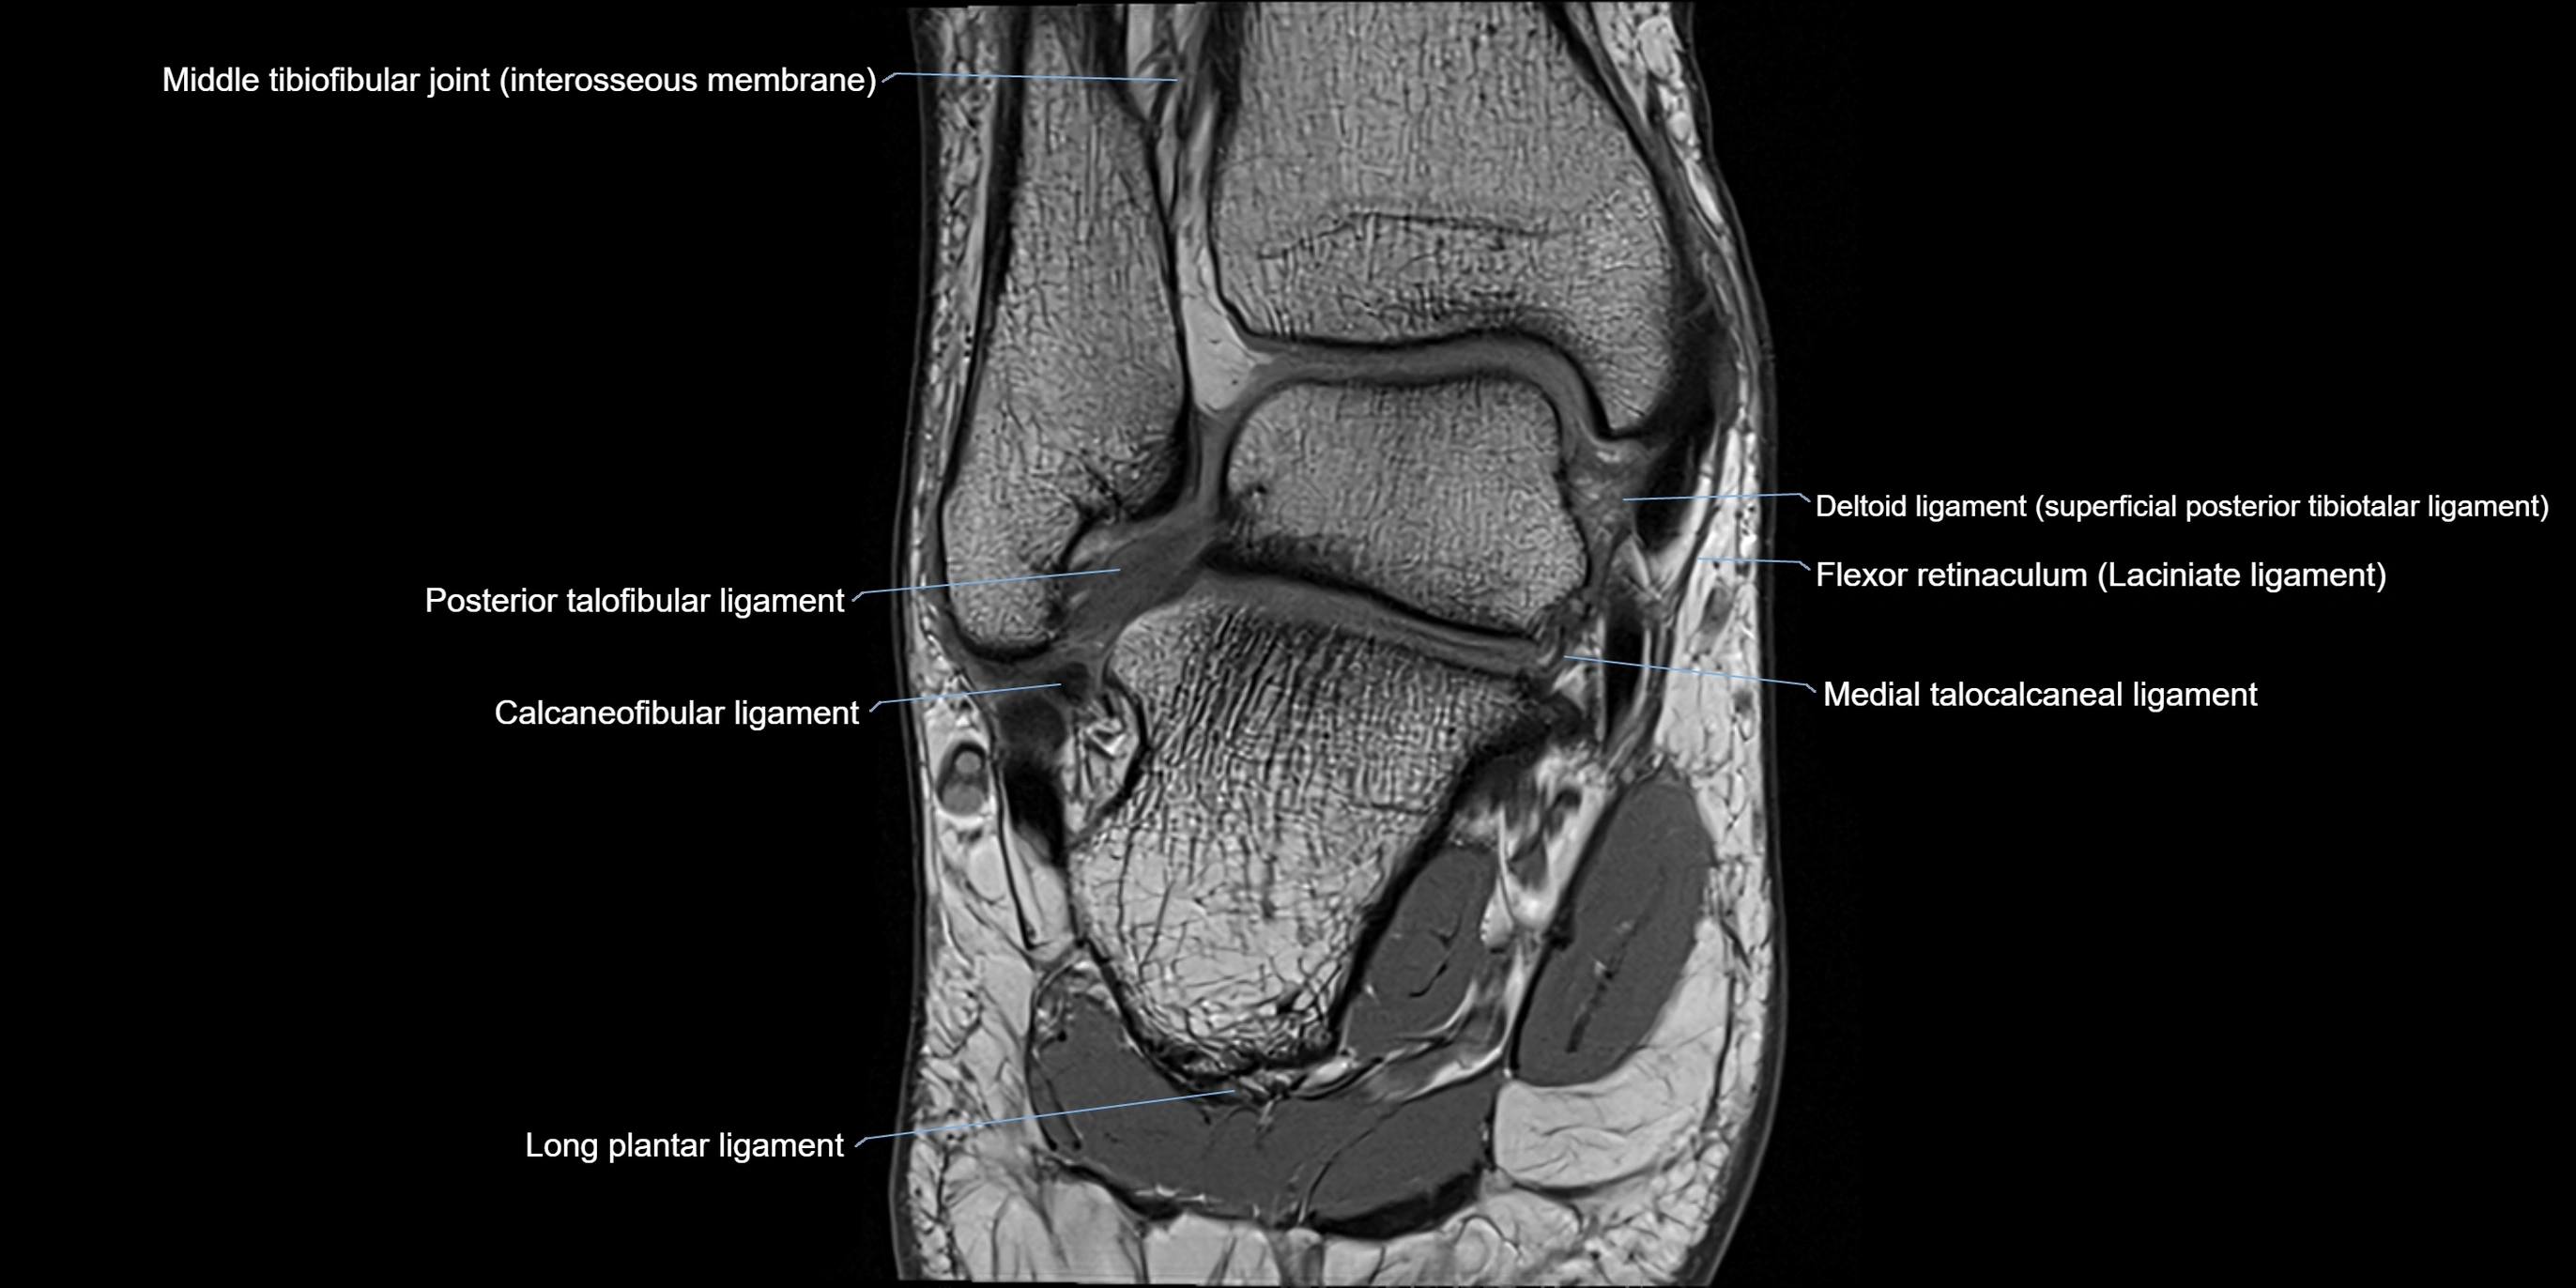

MRI image

image